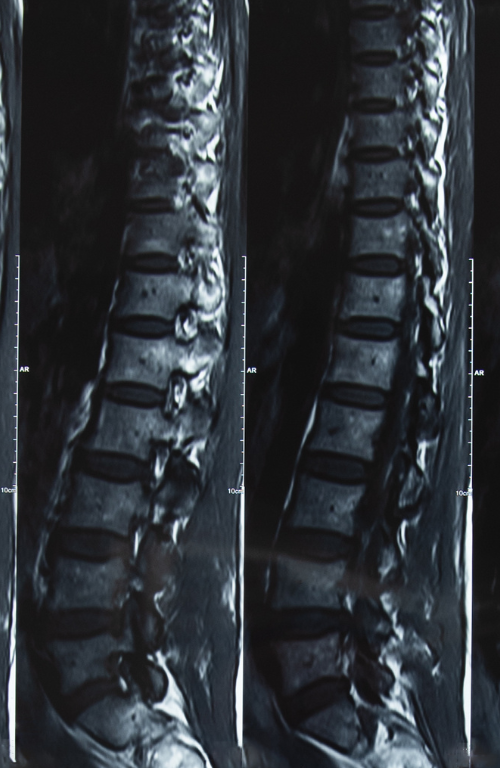

Discseel® Procedure 3DISCSEEL® ProcedureIs Hip Pain the Same as Herniated Disc Pain

Is Hip Pain the Same as Herniated Disc Pain

Hip pain can be combined with back pain. This can lead to lower back pain, groin and buttock pain, as well as knee pain. To describe people who experience pain…

Discseel® Procedure 1 1DISCSEEL® ProcedureDisc Herniation Causes Hip Pain

Disc Herniation Causes Hip Pain

A herniated disc refers to an issue with one of the rubbery cushions (discs)that sit between your bones (vertebrae)that stack to form your spine. The spinal disc is composed of a…